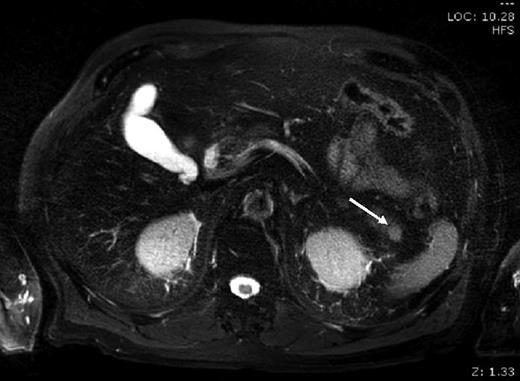

A 76-year-old male presented to his general practitioner with nausea, weight loss and change in bowel habit. A recent colonoscopy was unremarkable, a computed tomography (CT) abdomen and pelvis showed a homogenously enhancing 13-mm lesion in the tail of the pancreas, with the reported differentials including neuroendocrine tumour or a pancreatic adenocarcinoma. A subsequent magnetic resonance imaging (MRI) illustrated the lesion enhancing homogenously in the portal venous post-contrast phase suggesting a solid neoplastic lesion, likely to be primary (Fig. 1). He went on to have a distal pancreatectomy and splenectomy with an uneventful recovery. Pathology revealed a splenunculus with no evidence of malignancy (Fig. 2).

MRI: small round lesion in the pancreatic tail measuring 1×1 cm, enhancing homogenously in the portal venous post-contrast phase suggesting a solid neoplastic lesion. The differential includes primary pancreatic lesion such as a small mucinous cystic pancreatic tumour or an islet cell tumour